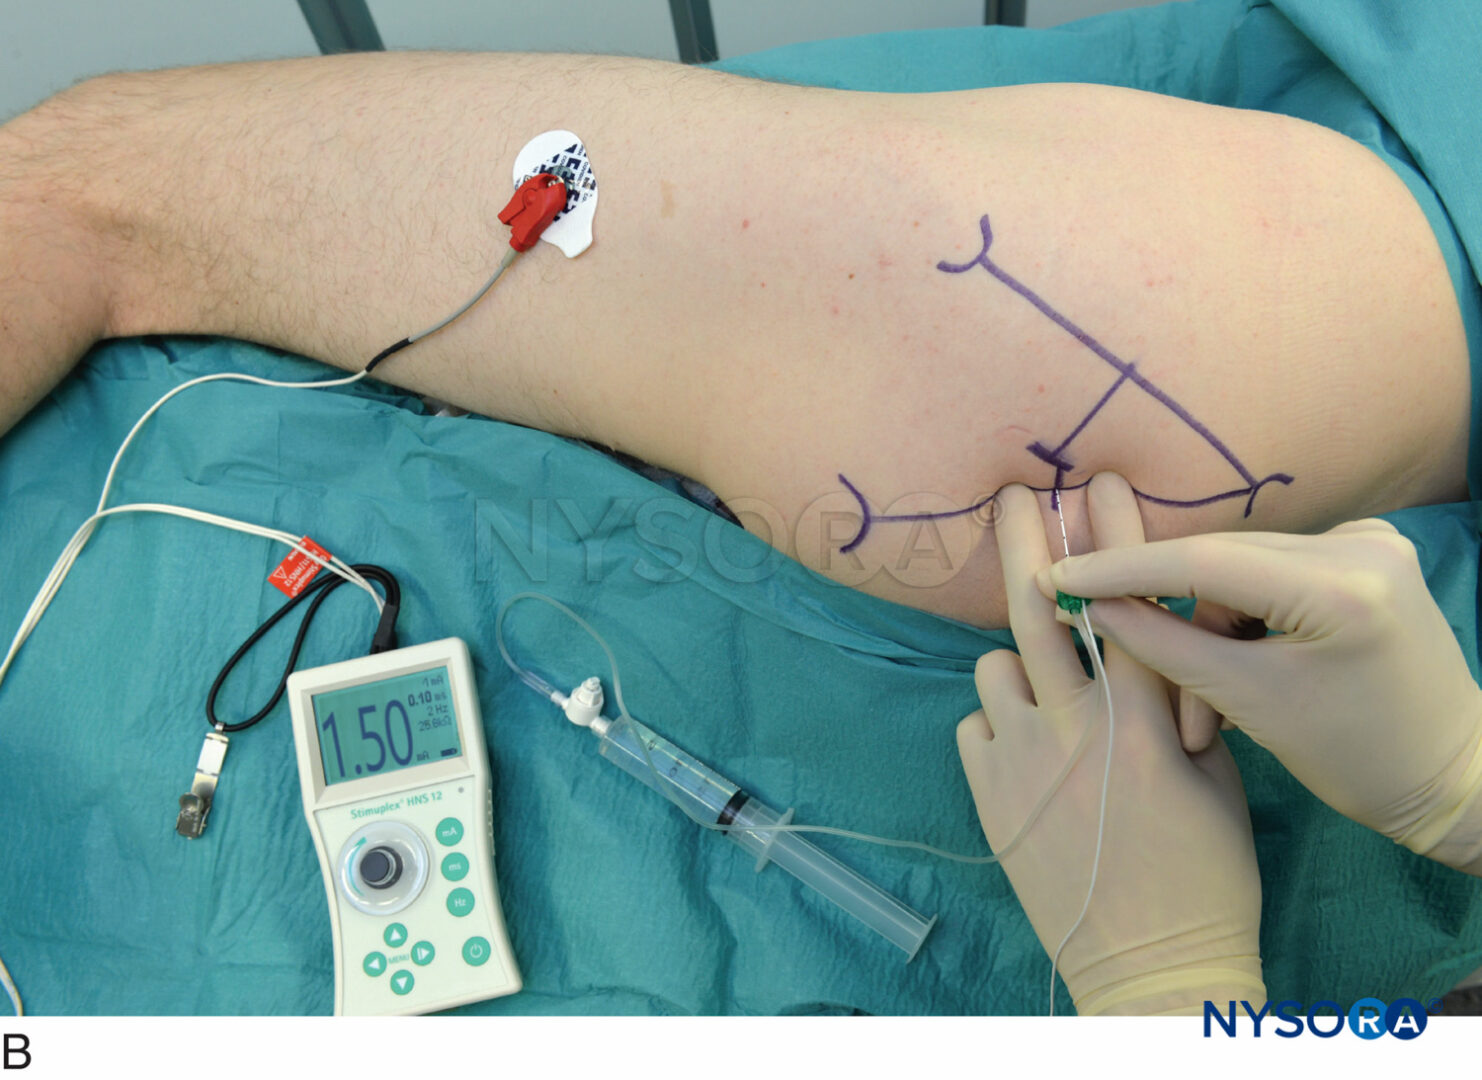

Amazon.co.jp: シンプルに打てる!外来での神経ブロック : 表。あっという間にうまくなる神経ブロック上達術|真興交易株式会社。肩の手術後の鎮痛のための横隔膜温存神経ブロック? パートI-NYSORA。斜角筋間神経ブロック - 連続カルーテル画像 | Sonosite。「シンプルに打てる!外来での神経ブロック」表 圭一定価: ¥ 7000#表圭一 #表_圭一 #本 #自然/医療・薬学・健康